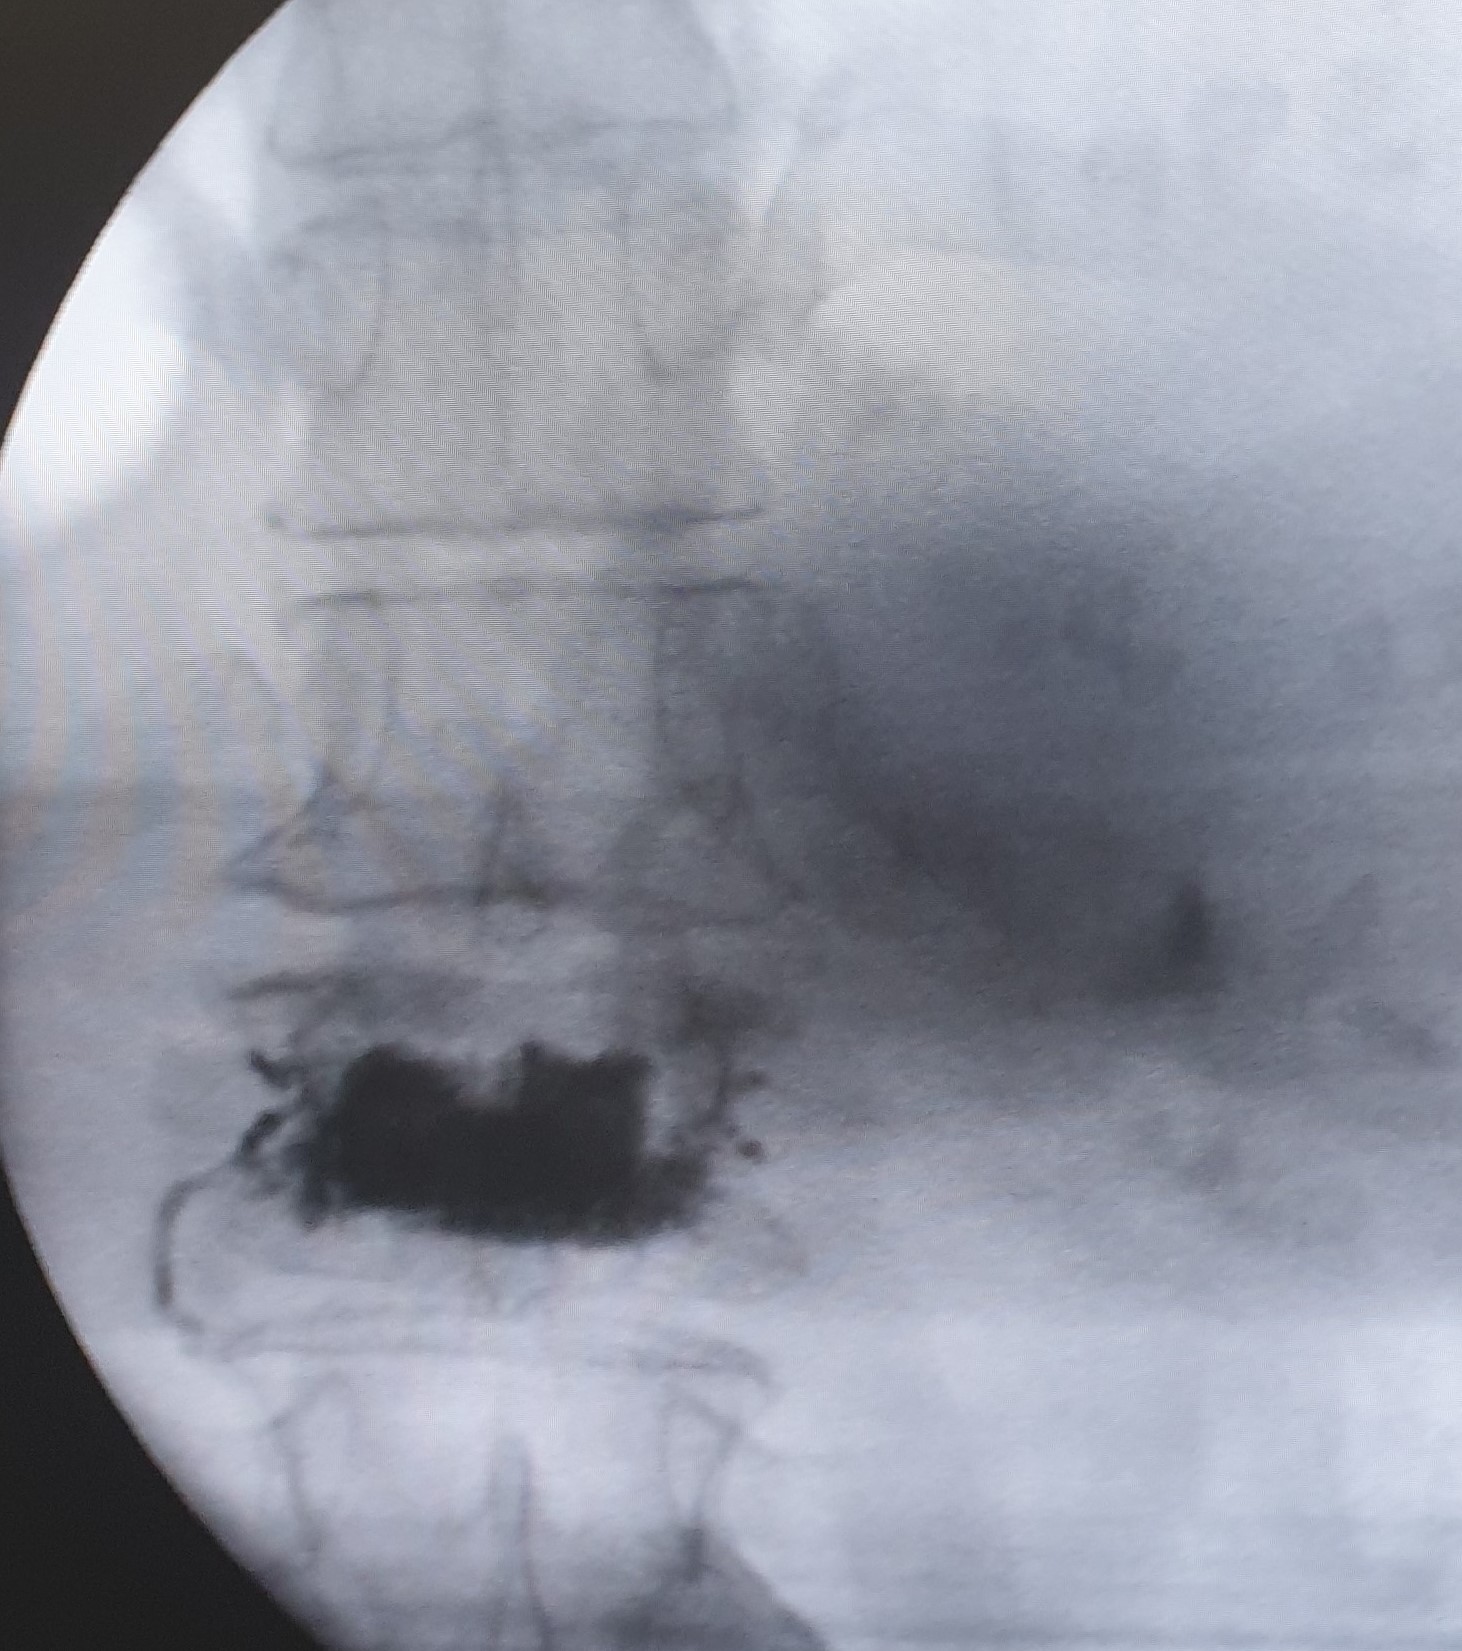

- Κυφοπλαστική και σπονδυλοπλαστική